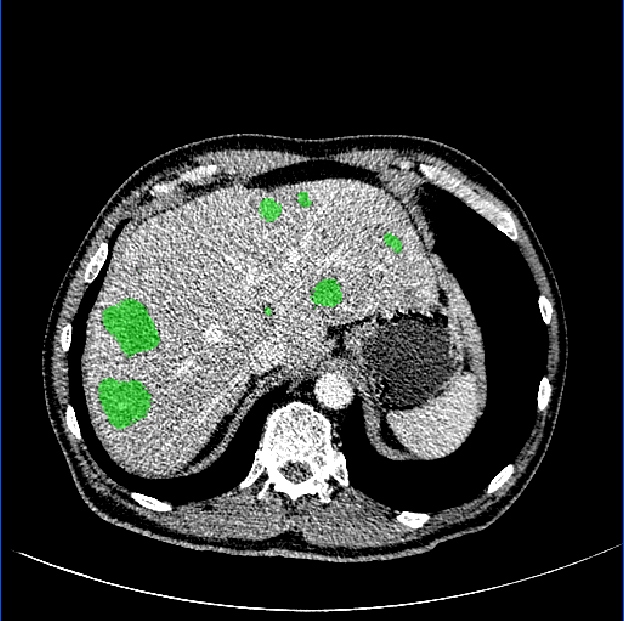

3.1 Comparison of Various Distance Maps Regression

A simple illustration of distance maps is shown in Fig. 2, which contains the binary segmentation mask, O-DM, inverse distance map (I-DM), NI-DM and sign norm inverse distance map (SNI-DM). I-DM is derived from the I-DM by taking inverse operation. SNI-DM is modified from the NI-DM, where the voxel inside the boundary of the target object is positive, otherwise is negative.

As shown in Fig. 3, our method demonstrates superior qualitative results, especially in the notoriously small tumors segmentation. In Table 1, the results show that the M-Net with the LR-Net achieves better performance than M-Net alone on all the evaluation criteria. This indicates indicates the significance of LR-Net on accuracy improvement. Then, we evaluate the performance of MapDice loss. By comparing the results with and without the MapDice loss, it is apparent that MapDice loss contributes a lot for segmentation accuracy improvement. In particular, the MapDice loss yields the superior results of NI-DM regression, while Dice loss shows a significant drop in the last four columns of Table 1. This indicates that distance map can help the network to capture semantically meaningful regions and produce more accurate reslults. The constant value , used to balance the magnitude difference of two different losses, is also verified to be effective for the performance improvement.